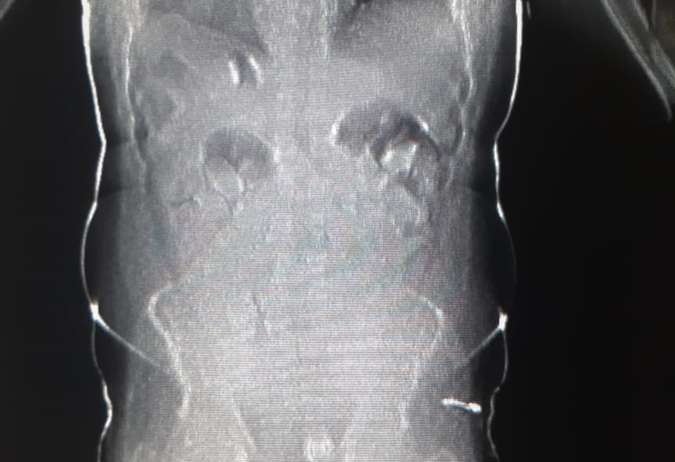

Imagem de raixo-x divulgada pela corporaçăo mostram as cápsulas dentro do corpo de um dos acusados. Eles responderăo por tráfico de drogas, crime com pena que varia de 5 a 15 anos de reclusăo.